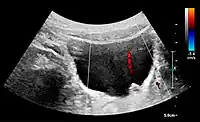

Under normal conditions, the ureter is not seen with US. However, in, e.g., urinary obstruction and vesicoureteric reflux with dilation of the ureter, the proximal part in continuation with the renal pelvis, as well as the distal part near the ostium can be evaluated (Figure 14).[1]

Figure 21. Left hydroureter with ureteric jet. No stone is visible. The red color in the color box represents motion towards the transducer as defined by the color bar.[1]